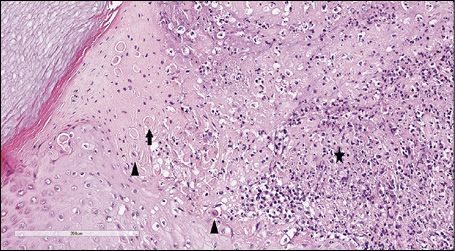

At scanning magnification, the histopathology showed a broad dermo-epidermal ulceration with an underlying purulent base (Figure 2). At higher magnification, the epidermis was characterized by necrotic keratinocytes with pycnotic nuclei and dense eosinophilic cytoplasm (Figure 3, arrowhead) and by scattered keratinocytes with a “shadow cell” appearance (enlarged cells with eosinophilic cytoplasm without well-defined nuclei [Figure 3, arrow]); suppurative changes were detected within the papillary dermis with marked neutrophilic exocytosis (Figure 3, asterisk). Some keratinocytes showed ballooning degeneration (Figure 4, arrow). An interstitial and perivascular/peri-adnexal inflammatory infiltrate composed of neutrophils and lymphocytes was observed in the deep dermis, associated with endothelial swelling (Figure 5, arrowhead) without fibrinoid necrosis of the vascular wall.

Figure 3 - Haematoxylin and eosin (H&E) stain. At higher magnification (40x), the epidermis was characterized by necrotic keratinocytes with pycnotic nuclei and dense eosinophilic cytoplasm (arrowhead) and by scattered keratinocytes with a “shadow cell” appearance (enlarged cells with eosinophilic cytoplasm without well-defined nuclei) (arrow); suppurative changes were detected in the papillary dermis characterized by marked neutrophilic exocytosis (asterisk).